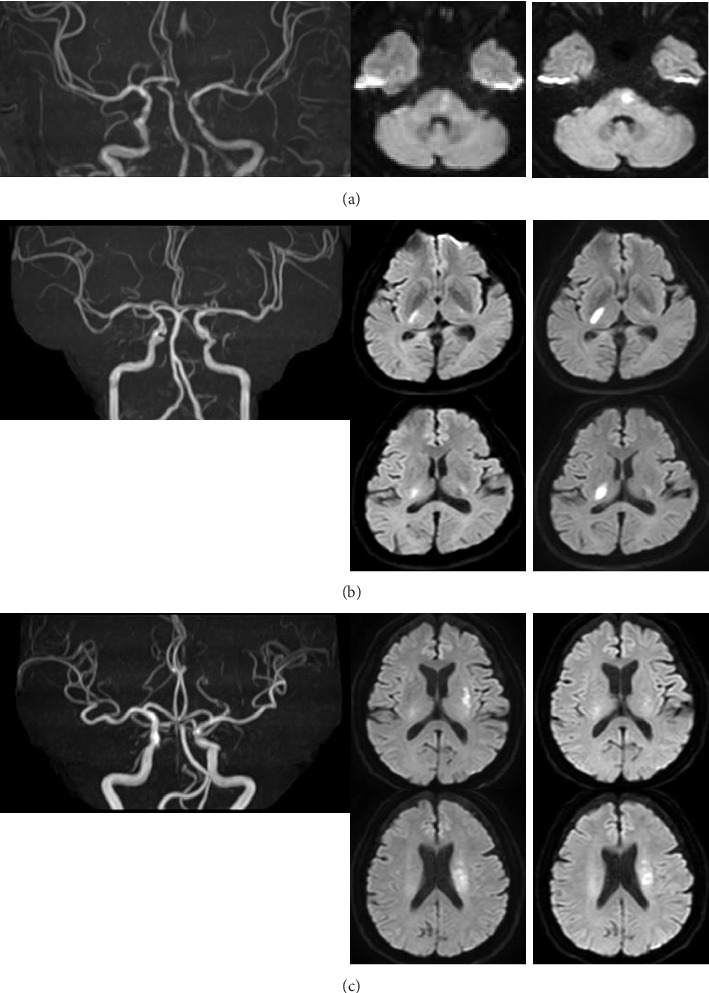

急性分支动脉粥样硬化患者通常在最初24小时内经历早期神经功能恶化(END),即使在静脉注射阿替普酶后也是如此。在静脉注射阿替普酶之前,用西洛他唑(一种磷酸二酯酶3抑制剂)治疗3例,目的是减轻END。3例患者均无出血并发症,3个月时预后良好,但有2例患者在静脉注射阿替普酶后24小时内出现END。

Patients with acute branch atheromatous disease often experience early neurological deterioration (END) in the first 24-h period, even after intravenous alteplase. Three cases treated with cilostazol, a phosphodiesterase 3-inhibitor, prior to intravenous alteplase with the aim of mitigating END are described. All three patients had no bleeding complications and good outcomes at 3 months, although two patients showed END within 24 h after intravenous alteplase.